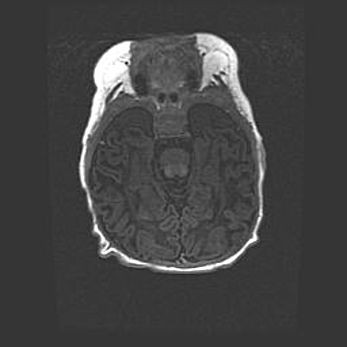

Открытая гидроцефалия.

Возраст: 9 месяцев 12 дней

Вес: 6800 г

Пол: мужской

Окружность головы: 41,5 см

Срок гестации: 28 недель

Гидроцефалия головного мозга у новорожденных имеет характерный признак: опережающий рост окружности головы приводит к визуально хорошо определяемой гидроцефальной форме сильно увеличенного в объёме черепа. Детские неврологи определяют следующие симптомы гидроцефалии у грудничков: выбухающий напряжённый родничок, частое запрокидывание головы, смещение глазных яблок к низу.